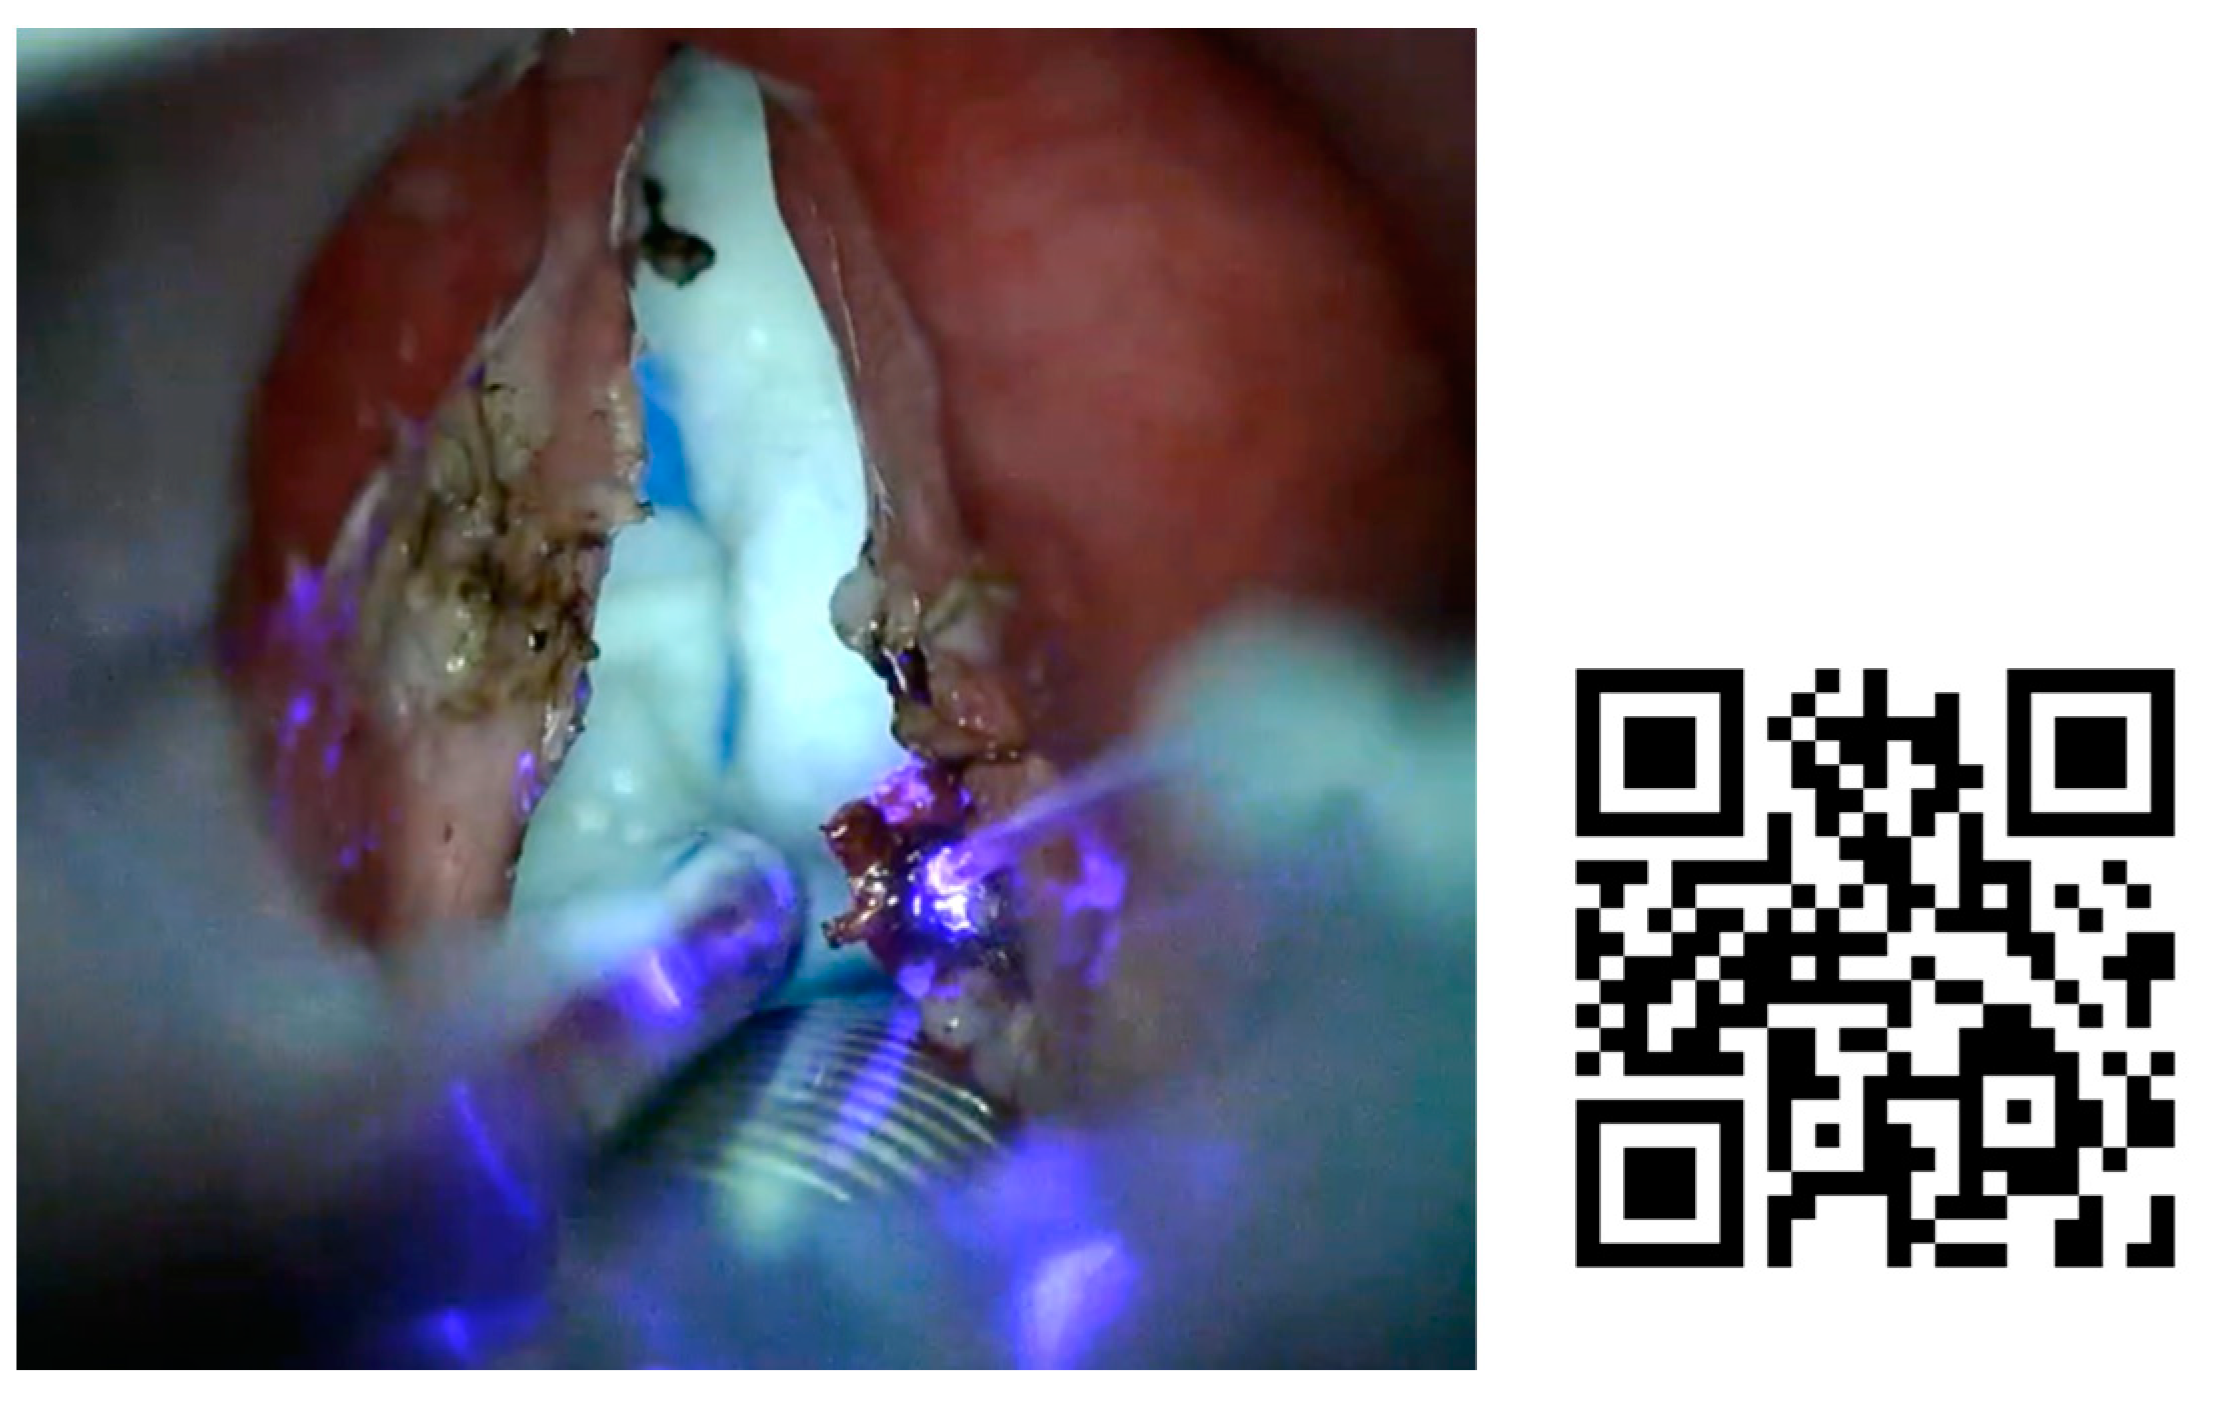

In Figure 5 can be seen a patient who came back after two years without lesions of papilloma, presenting new lesions in the glottis and supraglottis. We decided to treat under general anesthesia, to confirm diagnosis by a biopsy.

Figure 5. Laryngeal papillomatosis treated in the operating room with blue laser. A 34-year-old man with laryngeal papillomatosis in ENT follow-up for two years, presenting papillomatous lesions in the glottis and supraglottis. It was decided to treat these lesions in the operating room, to take a biopsy of the lesions and treat all visible lesions. Direct laryngoscopy and excision of the lesions was performed, using blue laser. After the intervention, bevalizumab was applied to the bed of the lesions to improve their control.